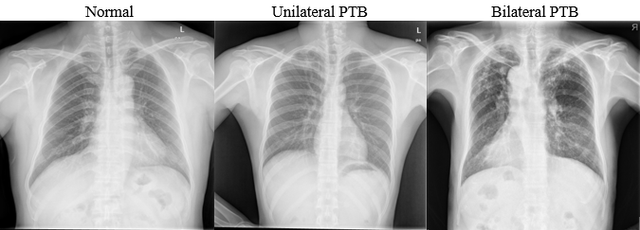

Penelitian ini menggunakan metode CNN sebagai pendekatan utama dalam pengklasifikasian citra medis. Data penelitian diperoleh dari dataset Chest X-ray Images for Tuberculosis (TBX11K) yang tersedia di Kaggle. Dataset ini terdiri dari 11.200 gambar X-ray paru-paru yang dikategorikan menjadi normal, Unilateral PTB, dan Bilateral PTB.

Hasil penelitian menunjukkan bahwa model CNN mampu mengklasifikasikan TB dengan akurasi tinggi. Pada tahap pertama (TB vs normal), model CNN mencapai akurasi 91%. Pada tahap kedua (Unilateral PTB vs Bilateral PTB), akurasi meningkat hingga 92%.